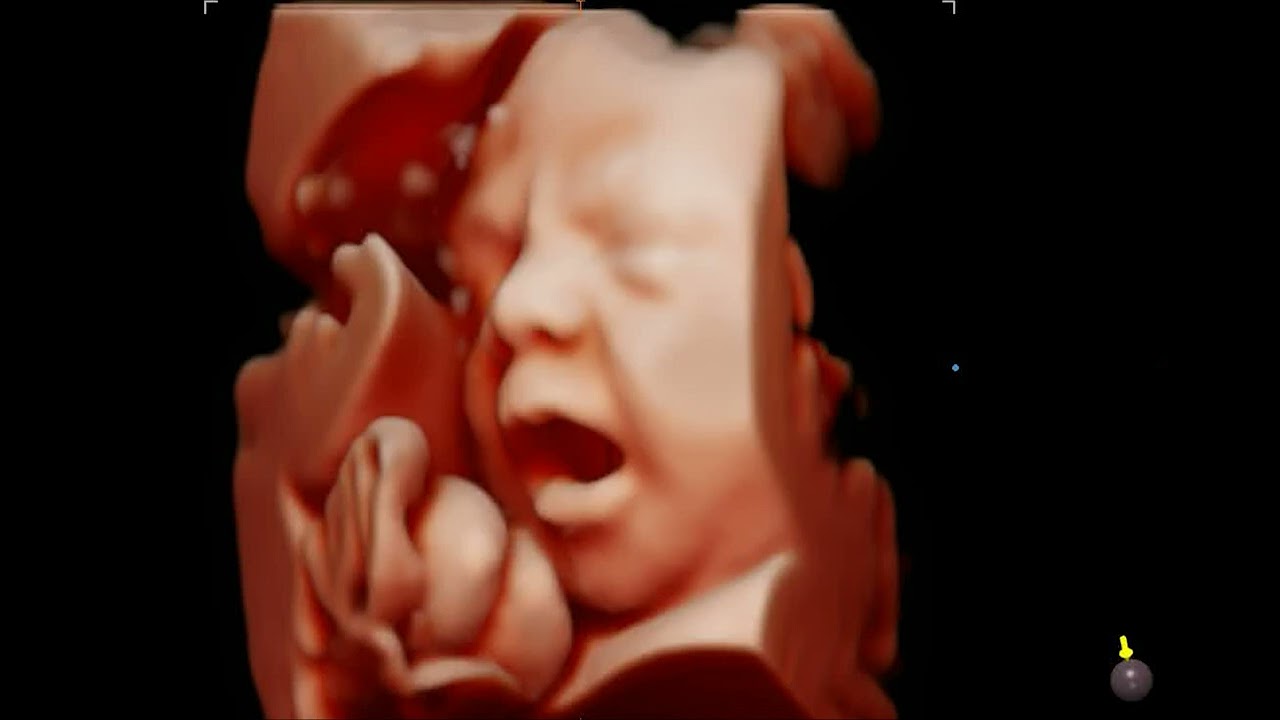

• Ecografia tridimensionale, Ecografia 3D e 4D

Tutte le ecografie vengono registrate sotto forma di video su chiavetta USB che la paziente può rivedere quando vuole a casa.

• Ecografia 4D

185 €